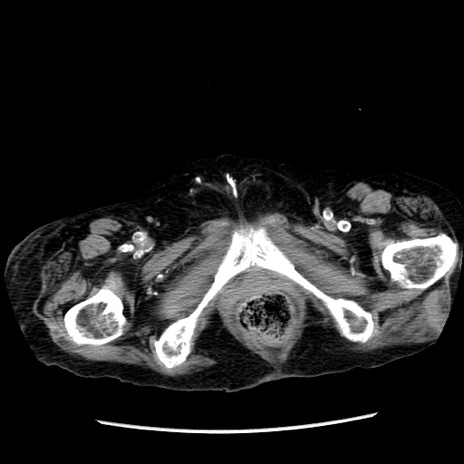

症例14(横断像)

【症例】 90歳代女性

【主訴】 腹痛・嘔吐

【現病歴】今朝から左側腹部痛を認めた。 経過観察していたが、嘔吐を認めたため来院。

【既往歴】 子宮癌術後

【身体所見】 意識清明、BP 127/54mmHg、P 98bpm Sp02 95%(RA)、BT 35.8°C、腹部平坦・軟腸ぜん動音聴取良好、右下腹部圧痛(+) 反跳痛なし

【データ】WBC 9800、CRP 0.46